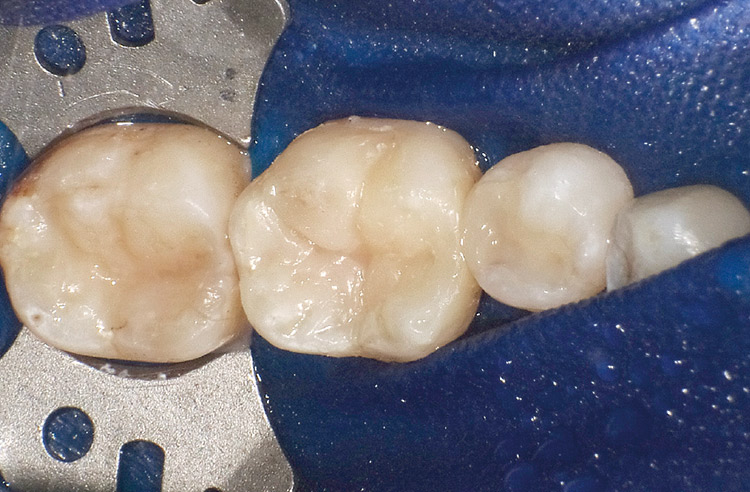

18. 術直後。隣接面の欠損が大きい症例においても、3Dリテーナー フュージョンLを用いたコンポジタイト3Dフュージョンにより、緊密な接触点を持つ適切な隣接面形態のコンポジットレジン修復を行うことができる(図34)。

図34 術直後

隣接面の欠損が大きい症例においても、3Dリテーナー フュージョンLを用いることで、緊密な接触点を持つ適切な隣接面形態のコンポジットレジン修復が可能。